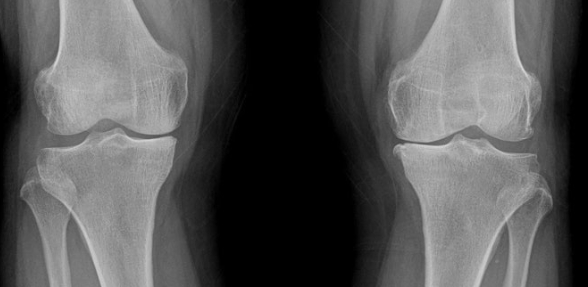

관절염의 본질은 관절 연골의 소모와 뼈 구조의 변형입니다. 따라서 수술 시기를 판단할 때 단순히 증상만 볼 것이 아니라, 영상검사를 통해 구조적인 손상이 어느 정도 진행됐는지를 확인하는 것이 중요합니다.

관절염은 일반적으로 1~4단계로 구분되며, 3~4단계는 수술이 고려되는 시기입니다. 이때 관절 간격의 소실, 골극 형성, 변형, 염증 등을 종합적으로 확인합니다. 특히 관절의 변형이 육안으로도 보이는 경우(안짱다리, 외반변형)는 수술 시기를 더 이상 늦추지 말아야 합니다.